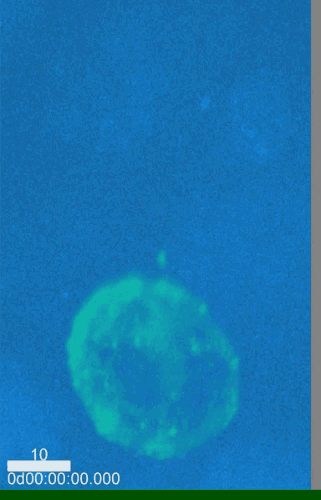

在发生性行为时,HIV是如何传给对方的?本周的《细胞·报告》期刊报道的一项突破性研究,让我们前所未有地看见HIV传播的全过程。这项研究还为艾滋病防治策略提供了全新的见解。 编译 | 施怿 审校 | 吴非 众所周知,性行为是艾滋病病毒传播的主要方式之一。但是,HIV是如何穿过生殖器粘膜,最终抵达免疫系统中的靶细胞的?我们却知之甚少。在先前的研究中,科学家主要从生化指标或形态学的角度去研究HIV传播的过程。 在《细胞·报告》(Cell Reports)杂志最新发表的一项研究中,来自法国第五大学的研究人员在他们构建的体外尿道粘膜模型中,运用实时成像技术,首次直观地看到了HIV在性行为中的传播过程。 “我们对HIV侵入人体组织的过程有着宏观的认识,但直接追踪活体组织中真实发生的情况是与前者完全不同的。令人惊喜的是,这项技术使得我们对整个过程中的每一步都有清晰的认识,”这篇论文的主要作者,巴黎第五大学的分子生物学家Morgane Bomsel说。 研究人员用绿色荧光蛋白标记HIV。当HIV感染T细胞时,如下面的视频所示,T细胞也能呈现绿色荧光。 HIV感染的T细胞 但是,正常情况下,你的T细胞显然不会通过性交行为进入性伴侣的体内。这是因为生殖器官中有一层上皮细胞起到屏障作用。那么,T细胞中的HIV是如何穿越上皮细胞,感染性伴侣的呢?视频为我们展现了这一过程。 在视频中,被绿色荧光蛋白标记的HIV感染的T细胞,与重建的尿道黏膜组织上皮细胞(蓝色)相遇。当被感染的T细胞和上皮细胞接触时,会形成一种在细胞表面突出的病毒学突触(virological synapse)结构。 T细胞细胞膜的重排刺激了可感染的HIV的产生,后者在视频中以绿色荧光点呈现。然后,就像科幻片里冲击枪发出的绿色荧光射线一样,病毒颗粒在电光火石之间通过突触穿过了黏膜上皮细胞。 值得注意的是,在这一过程中上皮细胞并没有被感染:病毒只是通过胞吞作用被裹在小泡里穿过了细胞。 而一旦它像这样穿过了整个上皮细胞层,就会被基质中的巨噬细胞所捕获。在观察影像的过程中,研究团队注意到一个惊人的现象:被感染的T细胞似乎直接瞄准了位于巨噬细胞之上的上皮细胞。“巨噬细胞就在那里静止不动,好像早就准备好了一样,只要病毒一从上皮细胞中逃逸出来,它就接收它们。这种现象让我们认识到突触总是在刚好位于巨噬细胞之上的上皮细胞上形成,这表明在巨噬细胞和上皮细胞之间确实存在相互作用。在此之前我们从没有观察到这样的影像,”Bomsel说。 被感染的T细胞(绿色)通过形成病毒学突触的方式使HIV颗粒被包裹在小泡中穿过上皮细胞层(蓝色)到达基质,随后这些病毒颗粒被等在基质中的巨噬细胞(红色)所捕获。 一两个小时后,一旦病毒产生和流出的过程结束,两个细胞的接触过程也结束,受感染的T细胞继续运动,寻找下一个感染对象。 被感染的T细胞移动并寻找下一个目标 这些被感染的T细胞存在于所有类型的生殖器官感染中。虽然游离病毒可以在黏膜的细胞间隙中游走,但它们穿透粘膜的效率比细胞内的病毒低得多,后者可以利用病毒学突触和胞吞作用穿越整个粘膜上皮细胞层。 HIV通过性行为传播的过程。1:被感染的T细胞(绿色)与新宿主上皮细胞(蓝色)接触。2:病毒学突触形成。3:HIV(绿色圆点)感染基质中的巨噬细胞(红色)。4:被感染的巨噬细胞释放病毒颗粒(黄色圆点)。5:HIV(红色圆点)长期潜伏在巨噬细胞中。 在接下来的20天里,这些巨噬细胞会继续产生并释放病毒,随后它们就进入了不产生病毒的潜伏状态,但病毒依然储存在这些巨噬细胞中。这为艾滋病治疗方案的研发带来了新的挑战:相比于已得到广泛研究的、HIV潜伏在血液T细胞里的过程,病毒经由生殖器粘膜进入巨噬细胞的过程的发生时间要早得多。 “一旦病毒潜伏在免疫细胞中,想要根除就会让情况变得非常复杂,”Bomsel说。虽然使用抗逆转录病毒疗法可以使病毒保持潜伏状态,但是一旦停止这种疗法,病毒就会停止潜伏并继续传播,“因此,我建议在感染病毒的早期就采取措施来避免病毒进入这种潜伏状态,这也是为什么我认为在粘膜上发挥作用的疫苗才是患者真正需要的。因为我们不能等。” 这是她的研究团队已经着手研究的课题。“我们正在想办法净化那些储存了病毒的细胞,因为一旦能够迫使病毒从这些细胞中出来,我们就能杀死它们。我们的另一部分工作是开发一种粘膜艾滋病毒疫苗,”她说。“这是个非常复杂的研究领域,但我认为它很重要。” 原始论文: https://www.cell.com/cell-reports/fulltext/S2211-1247(18)30570-9 参考链接: https://www.eurekalert.org/pub_releases/2018-05/cp-wha050218.php